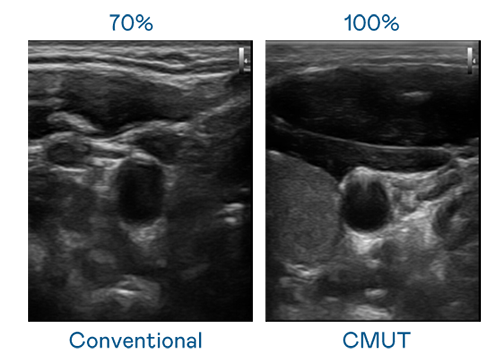

CMUT 技术是一种用电容式微机电元件来产生超音波讯号的技术。与传统 PZT 压电式技术相比,CMUT 频宽增加 30%,更宽频的超音波讯号让影像解析度大幅提升,是实现高影像品质医疗超音波扫描、促进精准医疗发展的关键技术。

大频宽带来超清晰影像

超音波影像的解析度高低,首先取决于探头能发出的讯号频宽。永利皇宫官网 CMUT 可提供高清晰的超音波讯号,提供高频宽、高灵敏度、影像纹理细节更高的超音波影像,协助医护人员缩短影像判读时间及利用精准的医疗影像进行诊断。